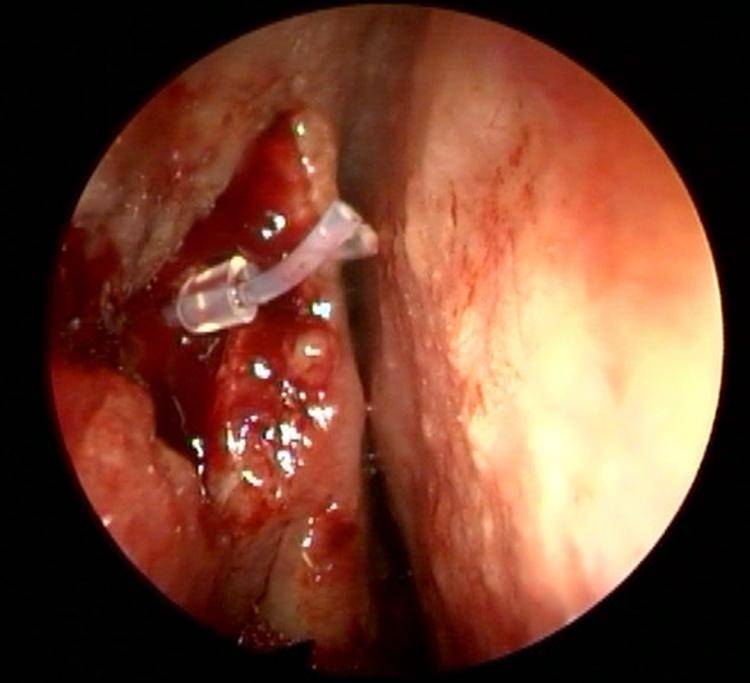

Dakriyosistorinostomi (DSR)’de silikon tüp serbest uçlarının, düğümleme yönteminden farklı bir teknik olan silikon kılıf kullanılarak sabitlendiği hastalar ile klasik düğümleme tekniği kullanılarak sabitlendiği hastaları operasyon sonrası semptomlar ve DSR başarısı açısından karşılaştırmak.

Gereç ve Yöntem: Epifora şikayeti ile başvurup kronik dakriyosistit tanısı alan ve tek taraflı endonazal DSR uygulanan 97 hastanın dosyaları tarandı. Silikon tüpün düğümlenerek sabitlendiği hastalar ve silikon kılıfla sabitlendiği hastalar olmak üzere iki grup oluşturuldu. Erken ve geç dönem kontrollerdeki sonuçlar kaydedildi. Epifora varlığı, silikon tüpe bağlı irritasyon semptomları ve lakrimal drenaj sisteminin açık olup olmaması ile ilgili bilgiler kaydedildi.

Sonuç: Silikon kılıfla sabitleme, irritasyon şikayetinin daha az olması ve daha iyi fiksasyon sağlaması açısından düğümleme yöntemine alternatif olabilir.